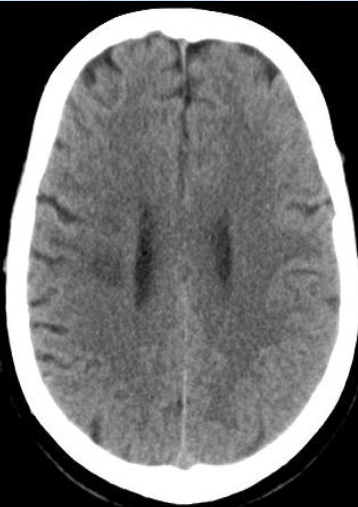

术后即刻、14小时与18小时复查头颅CT

病历夹什么径技·第152期|串联营病历夹:川陕大营_https://www.jmylbn.com_新闻资讯_第29张

病历夹什么径技·第152期|串联营病历夹:川陕大营_https://www.jmylbn.com_新闻资讯_第30张

病历夹什么径技·第152期|串联营病历夹:川陕大营_https://www.jmylbn.com_新闻资讯_第31张

病历夹什么径技·第152期|串联营病历夹:川陕大营_https://www.jmylbn.com_新闻资讯_第32张

<<滑动查看下一张图片>>

术后情况

呼之能应,言语欠清,四肢可见肢体活动。

查体:神志嗜睡状,言语欠清,双瞳等大形圆直径1.5mm,光反射迟钝,双眼可见眼球活动,伸舌居中,四肢肌力2+级,四肢肌张力不高,双侧病理征阳性。NIHSS评分15分(意识1分+意识水平提问1分+意识水平指令1分+凝视1分+视野1分+面瘫0分+上下肢运动6分+感觉2分+语言1分+构音障碍1分)。